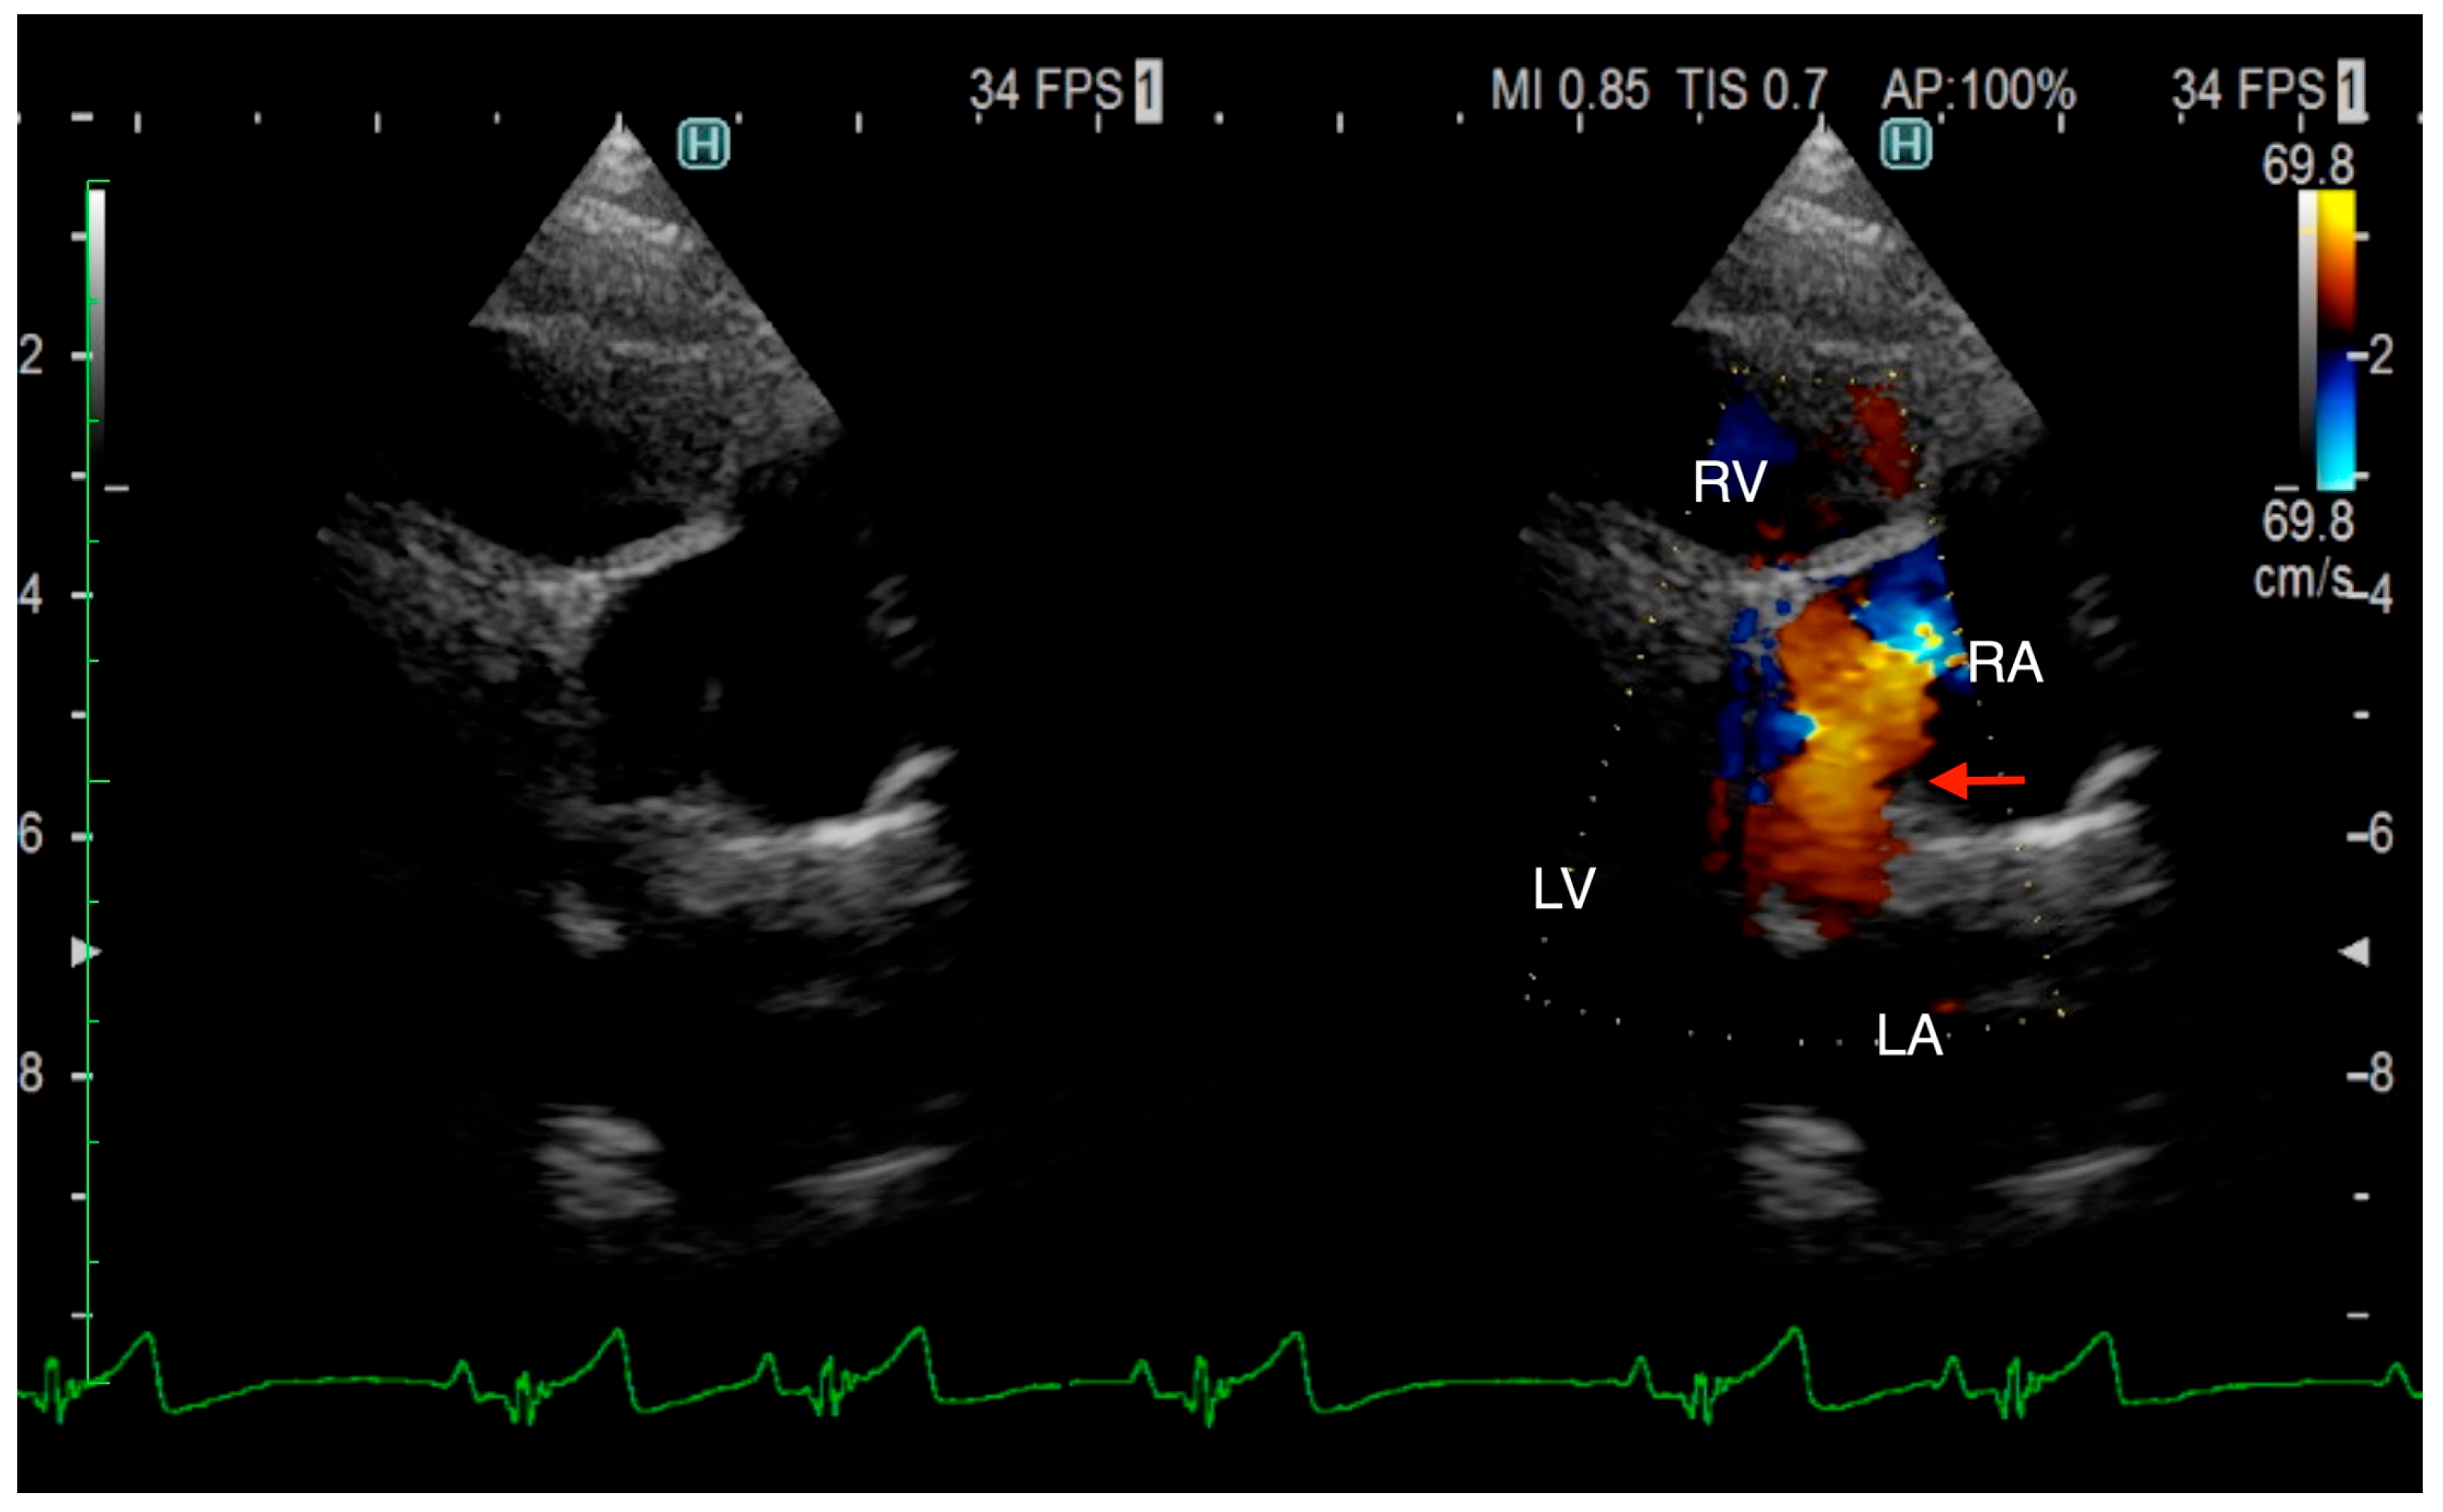

The TTE was performed using LISSENDO 880LE (Fujifilm Ltd., Tokyo, Japan) equipped with the 9–12 MHz phase array transducer probe (Fujifilm Ltd., Tokyo, Japan). TTE revealed trivial tricuspid regurgitation (TR), a pulmonary to systemic blood flow ratio (Qp/Qs) of 1.28, and there were no signs of a flattened ventricular septum. A left-to-right shunt, indicated by an irregular blood flow from the vicinity of the LA to the RA, was seen, although based on the evidence given at that time, it was possible that the blood flow was not actually within the heart. Conclusively, ASD was strongly suspected, although there was no opening found at the typical location during the TTE (Figure 1). Otherwise, the TTE evaluation revealed that other parameters were within normal limits. The results from the TTE were insufficient for a definitive diagnosis, so plans were made to further investigate with an ECG-gated CT.

Figure 1. Right parasternal long-axis four-chamber view of transthoracic echocardiography at the time of arrival. Transthoracic echocardiography shows an irregular communication between the left atrium and right atrium (arrow). From this image, it is unclear whether the blood flow is within the heart. RA, right atrium; RV, right ventricle; LA, left atrium; LV, left ventricle.